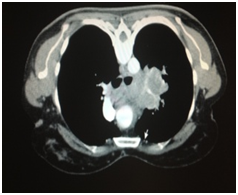

A subsequent CT Thorax/Abdomen/Pelvis (CT TAP) revealed a large mass encasing the left pulmonary artery with multiple lymph nodes and lesions on the liver (Figure 2). Further ultrasound indicated simple liver cysts (Figure 3). An ensuing Endobronchial ultrasound indicated squamous cell carcinoma with extensive necrosis; this finding was confirmed by bronchial washings. Finally, a PET CT disclosed uptake in the upper lobe with extensive mediastinal involvement, pleural metastasis, and chest wall invasion. There was no liver or bony involvement. The patient was not suitable for surgical treatment and was referred to the Medical Oncology team.

Figure 2 CT Thorax showing a mass encasing left pulmonary artery.